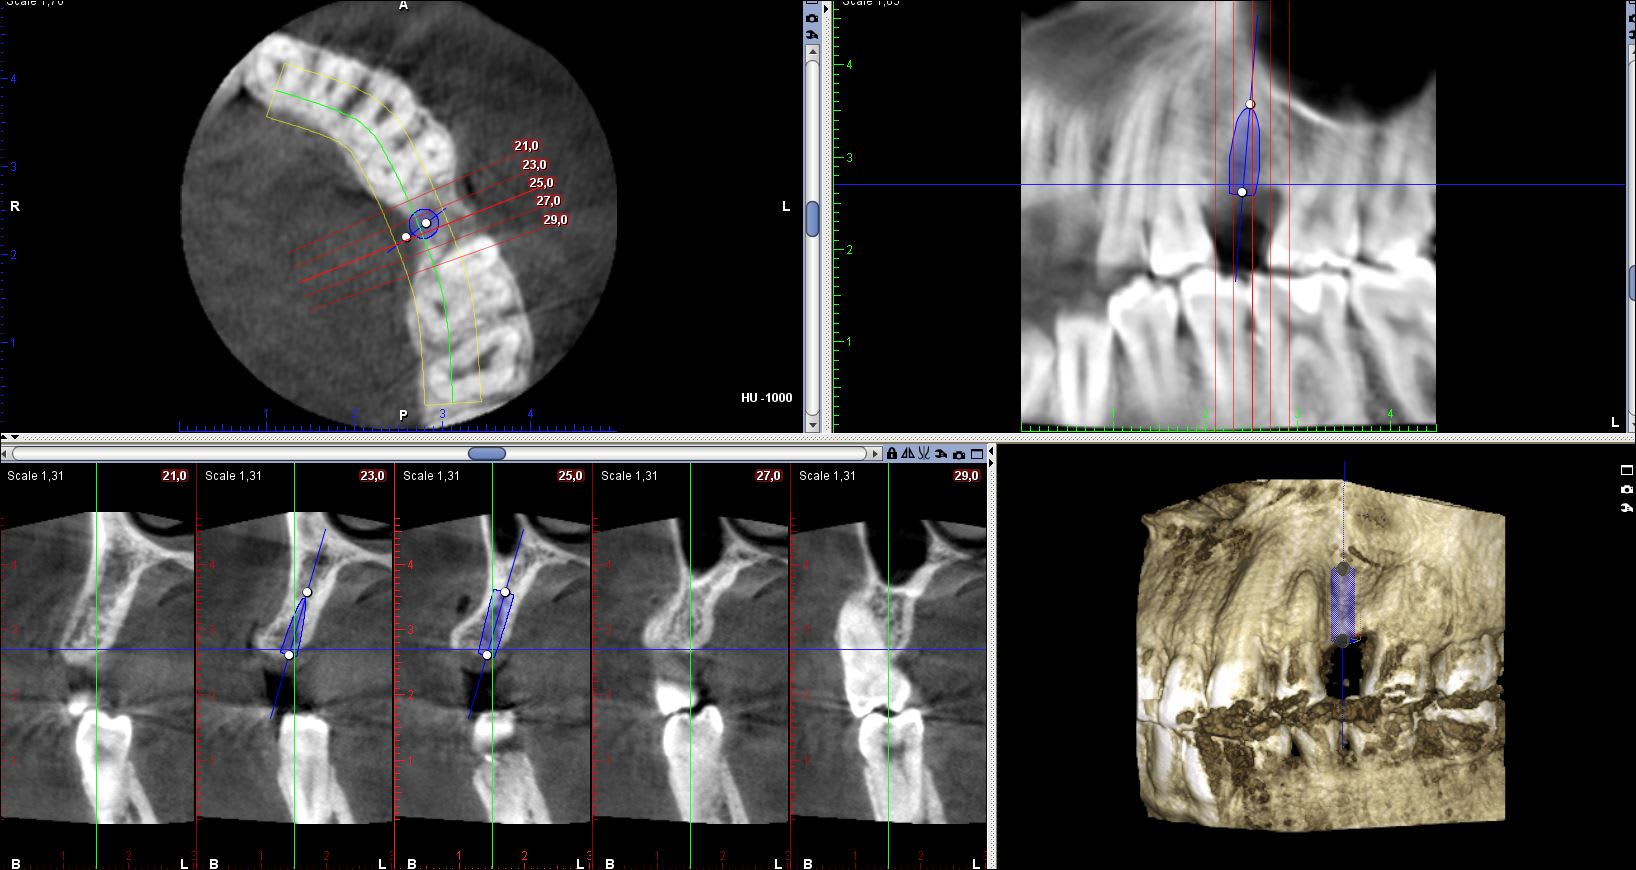

Comme vous voyez sur le 3D une belle concavité en Vestibulaire, je prépare prudemment sans fenestrer pense-je à cette instant.

Un peu bizarre quand même, au niveau épaisseur ce n'est si mal que ça d'après les coupes.. Tu es sur que tu n'a pas foré et transpercé en vestibulaire? Une 3d avant dépose de l'implant nous aurait été bien utile...

Au niveau apical tu n’as pas d’épaisseur d’os.

Peut-être une perforation de la corticale vestibulaire ?